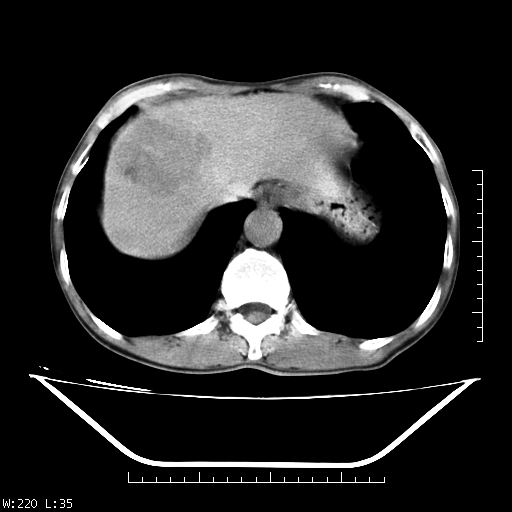

男,70,右上腹痛两月,有乙肝病史,b超提示肝占位,ct如下,请会诊。

补充:该患者afp9.24

肝右叶类圆型密度减低影,密度不均,边界清晰其内可见更低密度影,腹膜后可见小淋巴结肿大,增强扫描动脉期病灶明显强化,静脉期及延时扫描见强化不明显,快进快出表现。

1.肝右叶低密度影考虑为肝癌;

2.肝转移待除外。

平扫呈低密度占位,动脉期斑片状明显强化,病灶边缘清晰,见假包膜;门脉期呈低密度,符合肝癌快进快出强化特征

补充:该患者afp 9.24,似乎与原发性肝癌不符合,另胰头区结构正常吗?请大家继续发表高见。